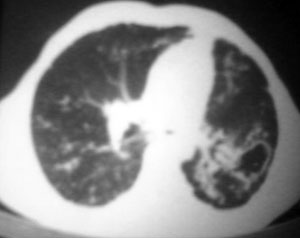

以下是引用逸风在2006-9-12 14:57:00的发言:[br]ct显示双肺上叶点片状及纤维索条状密度不均影,肺野外带近胸膜可见大小不等的含气空腔,壁略厚,境界清晰,未见液平面,中下肺野散在小片状及点状高密度影;纵隔内显示点状钙化,未见明显淋巴结肿大,构成胸廓诸骨未见明显异常.[br]诊断意见:1.双肺结核合并支气管播散;2.双肺上肺大泡.